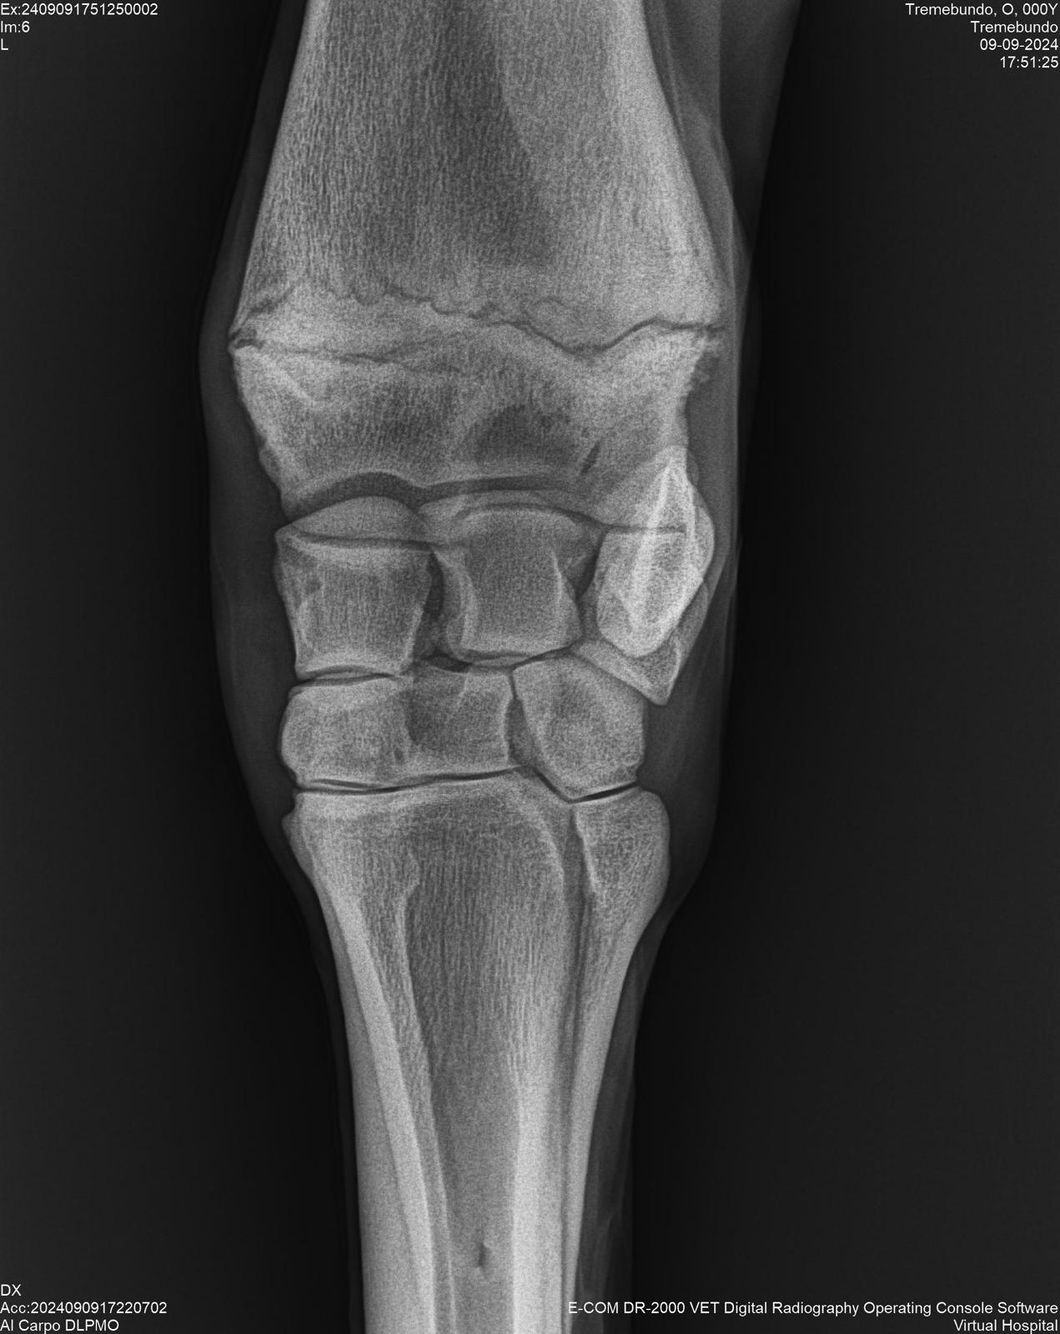

LOTE 37, TREMEBUNDO

Identificador: #291140-

Generacion 2022